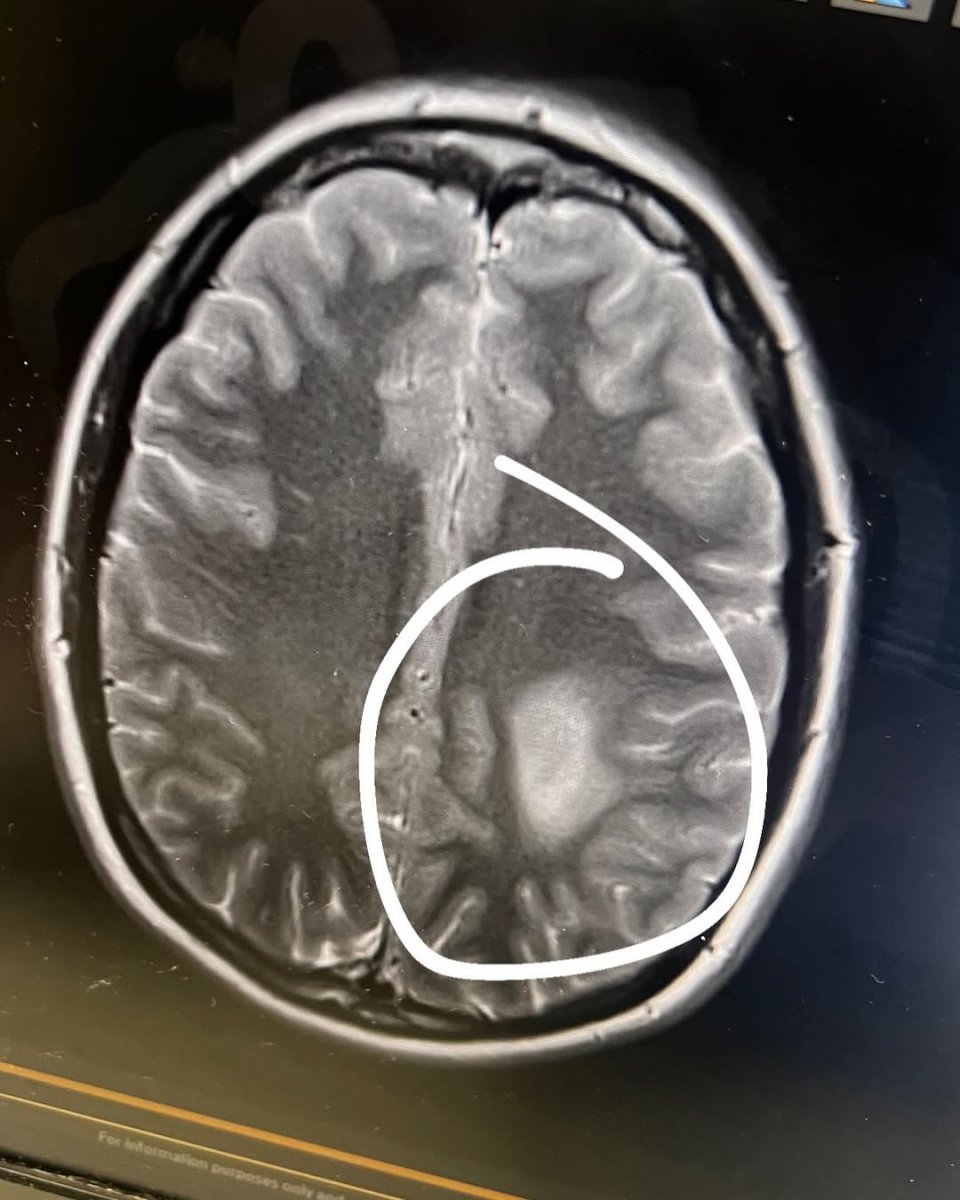

Galéria k článku Mladej žene povedali, že ZOMRIE na rakovinu: Lekári nechápu! Veľký nádor ZMIZOL

Zdroj: Instagram.com/journey_through_cancer